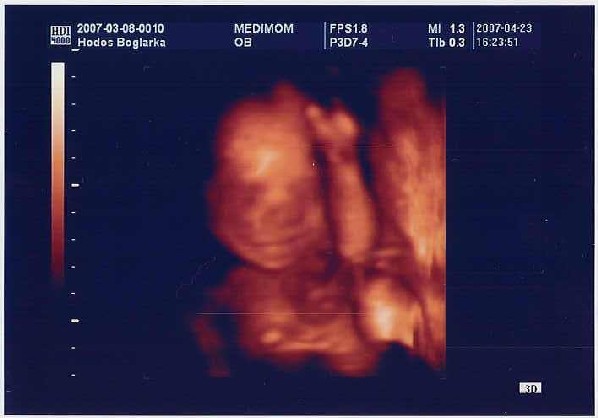

Times, aranyos kis pocid van, már jól látszik